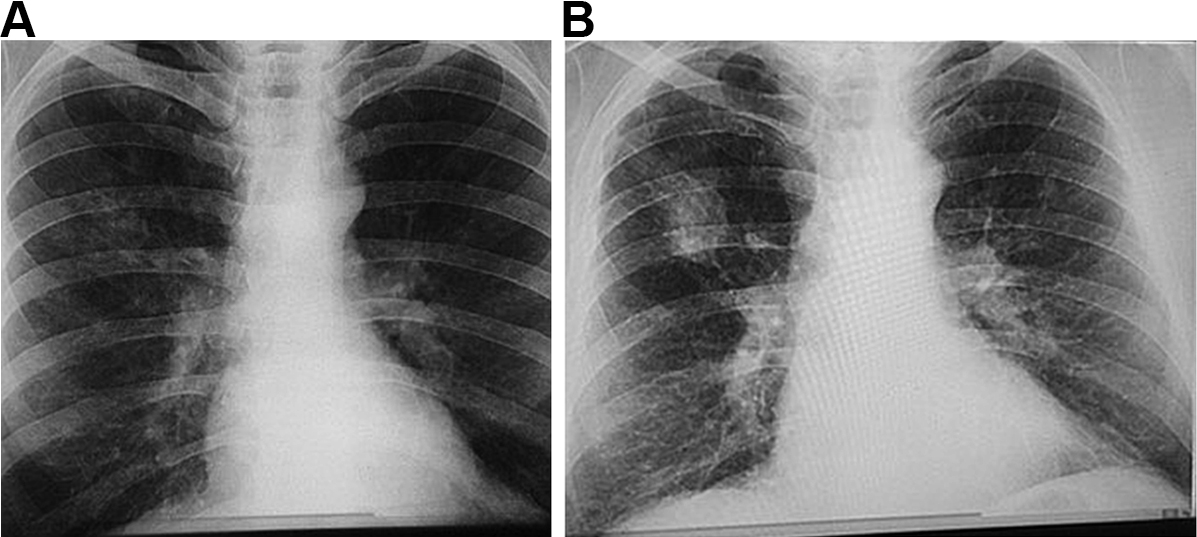

The manifestations of CWP can vary greatly between individuals, depending on the composition of the dust and duration of exposure, as well as host-related factors.34 Accumulation of dust occurs initially in the walls of the respiratory bronchioles, the adventitia of the blood vessels and the bronchoalveolar canals. Collections of dust-laden macrophages accumulate in the walls of the airways, particularly at their bifurcations, and in adjacent alveoli.1 Fibrous tissue is deposited, which later shrinks and leads to distortion of local lung structures.34 With increasing release of inflammatory mediators and deposition of fibrous tissue, these “macules” become larger and develop into more organised, dense, central, dust-pigmented lesions called micronodules,1 which can be palpated in the lung and seen on a chest x-ray (Box 1). Many larger rounded nodules then develop, particularly in the mid and upper zones of the lungs. Subsequently, centriacinar emphysema develops.35

Eventually, large masses of coal dust (Box 2), lymphocytes, dust-laden macrophages, reticulin and collagen may converge to form areas of PMF. These usually occur in the upper posterior parts of the lungs and appear as large rounded masses on the chest x-ray34 (Box 1, B). The presence of PMF represents “complicated” CWP and is associated with increasing symptoms and mortality.34

Box 1 – Chest x-rays of a coal worker (A) showing background nodulation and early progressive massive fibrosis (PMF) in the right upper zone, and (B) 12 years later, showing PMF